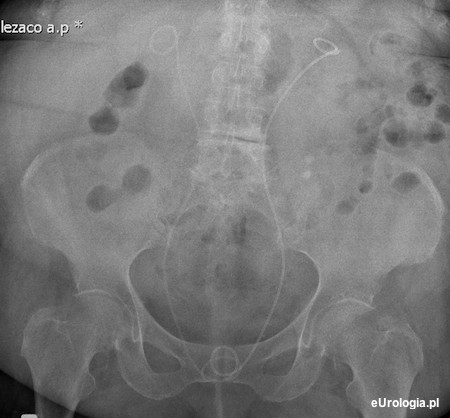

Wodonercze obustronne u pacjentki z wypadaniem narządu rodnego

Moja teściowa trafiła do szpitala z powodu niewydolności nerek. W wykonanych badaniach postawiono rozpoznanie wodonercza obustronnego i wypadanie narządu rodnego. Mamie zparoponowano operacyjne usunięcie macicy ze względu na zmiany o charakterze mięśniaków. Jako leczenie doraźne zastosowano cewniki JJ założone do obu moczowodów. Czy cewniki moczowodowe JJ są często stosowane w takich przypadkach jak ten?